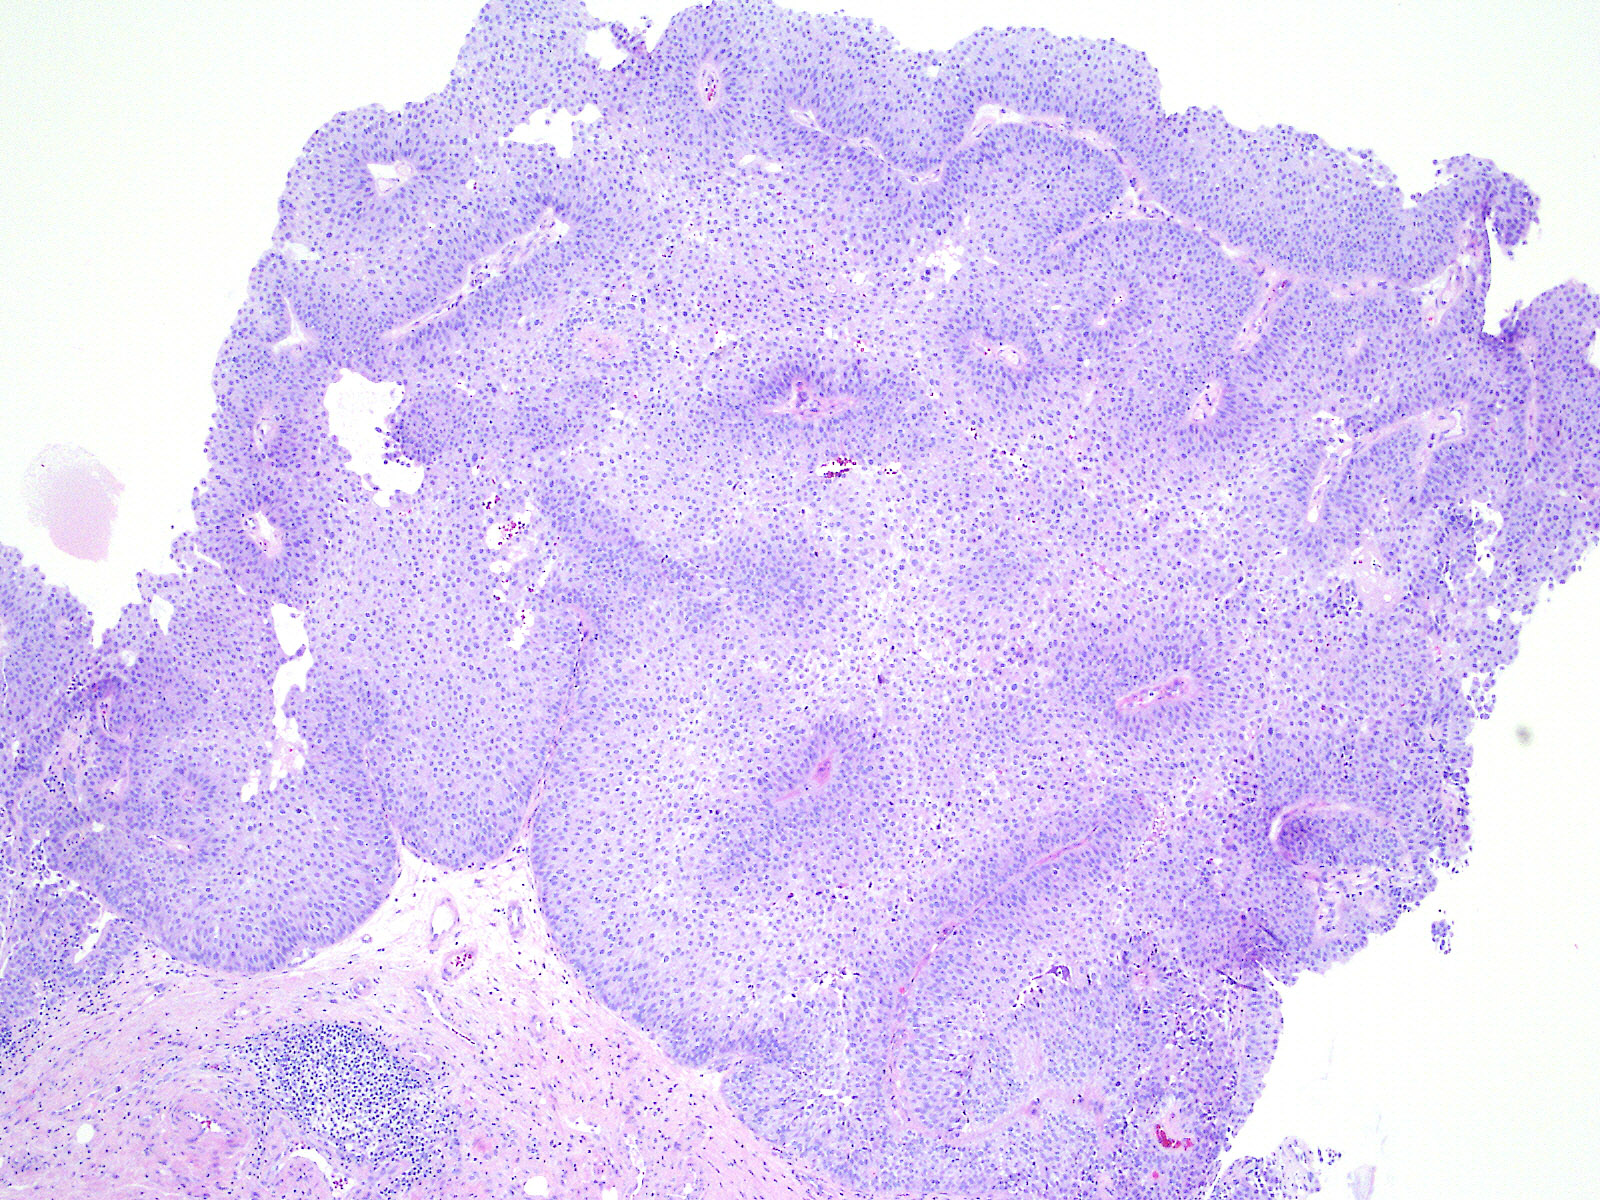

Bladder Papillary Lesions

Case ID: 526